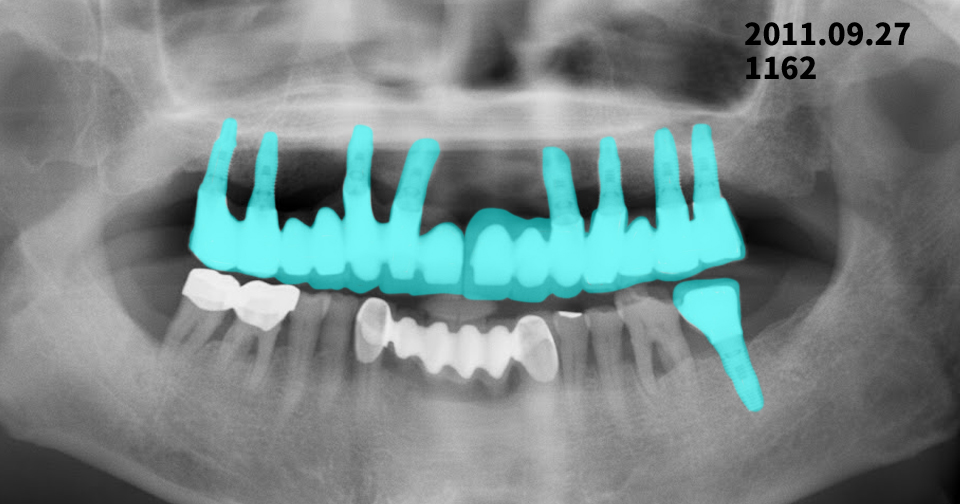

임플란트 14년 경과 후 치조골 변화

2011년 식립 → 2025년 정기검진 X-ray 비교 | 광진구치과

2011년 임플란트 식립 후 약 14년이 지난 2025년 정기검진 파노라마 X-ray를 통해

임플란트 주위 치조골 변화를 추적 관찰한 사례를 소개해 드리겠습니다.

검사 개요

- 2011년 : 임플란트 식립 후 파노라마 X-ray 촬영

- 2025년 : 정기검진 파노라마 X-ray 촬영

- 비교 항목

- 임플란트 주위 치조골 높이 변화

- 골 소실 여부

- 장기 안정성 평가

상악(윗턱) 임플란트 변화

2011년과 2025년 파노라마 X-ray를 비교해 보면,

- 임플란트 나사산 주변의 골 접촉 상태가 전반적으로 잘 유지

- 임플란트 목 부위에서 관찰되는 경미한 골 흡수는

장기 사용 임플란트에서 흔히 나타나는 생리적 변화 범위

여러 개의 임플란트가 보철물로 연결된 구조로

저작력이 비교적 고르게 분산되어 안정적인 상태로 판단됩니다.

하악(아랫턱) 임플란트 변화

하악 후방 임플란트 부위에서도

- 2011년 대비 뚜렷한 치조골 감소 소견 없음

- 임플란트 주위에 염증을 의심할 만한

방사선 투과성(검게 보이는 부위) 소견은 관찰되지 않음

👉 현재 영상 기준으로는

임플란트 주위염을 강하게 의심할 소견은 없는 상태입니다.

14년 경과 임플란트, 종합 평가

✔ 임플란트 식립 후 10년 이상 경과한 사례

✔ 급격한 골 소실이나 임플란트 실패 소견 없음

✔ 정기검진과 관리가 잘 이루어진 예후가 좋은 케이스